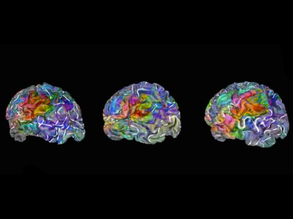

Rainbow Brain Rows